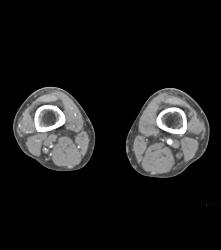

Small Caliber Aorta With Hardware Screw Abutting Aorta